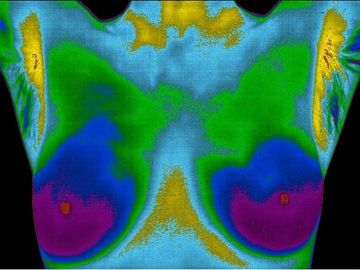

This image shows large, hot, red-orange blood vessels across the upper quadrants of both breasts. Upon further testing, the patient was diagnosed with mammary estrogen dominance. Many patients with this condition have tenderness, pain, fibrocysts, and/or cystic breasts. One of the leading risk factors for breast cancer is long-term exposure to synthetic estrogen. See "What Are Hormone Disruptors?" below.

The pre-treatment image above shows a pattern of large, hot (red) blood vessels across both breasts. Her doctor diagnosed her with mammory estrogen dominance.

The post-treatment view above shows a complete resolution of the previous hyperthermic vascular pattern. The image is now displaying a relatively cool and normal pattern across both breasts.